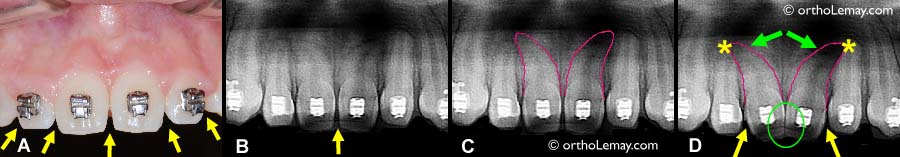

Fermeture d’espace en « V » entre des incisives

• (A) Espaces interdentaires (embrasures) en “V” entre des incisives supérieures de forme ovale (flèches).

• (B) Radiographie montrant la forme des dents et l’espace entre elles.

• (C) Même radiographie qu’en (B) avec le profil des racines des incisives centrales tracé en rouge. Ces racines sont plus courbées que la normale.

• (D) Simulation d’un mouvement de bascule des couronnes des centrales vers le centre pour créer un contact plus long entre les dents et diminuer l’espace en “V” (cercle vert). L’effet secondaire de ce mouvement est qu’un espace plus grand apparaît entre les centrales et les latérales (flèches jaunes) et que les racines des centrales sont basculées vers celles des latérales (flèches vertes) et entrent en collision avec elles (* jaunes). Ce type de mouvement n’es pas recommandé à cause du dommage qu’il peut causer aux racines des dents.